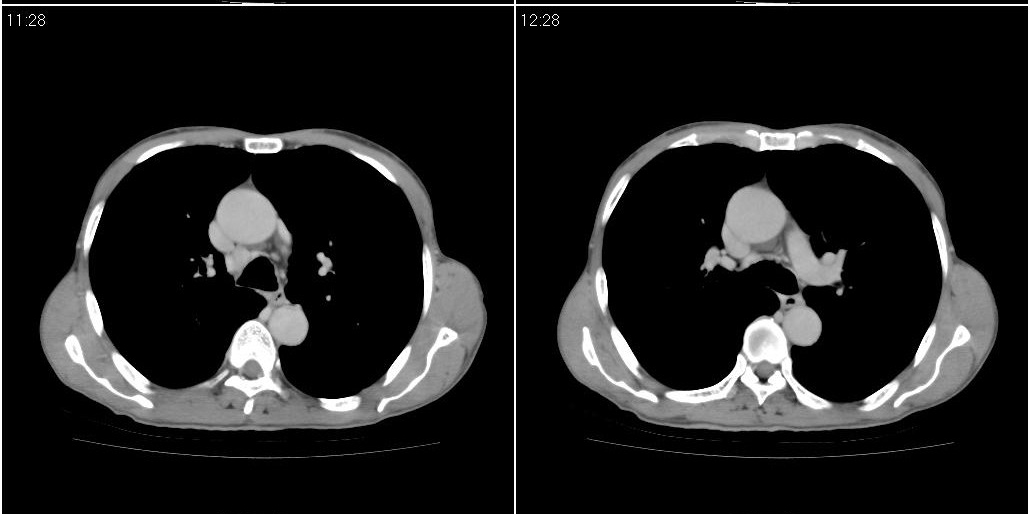

标题: ct增强:

1)右肺中叶慢性炎症并支气管扩张,节段性肺不张。2)两肺下叶支气管扩张。

1)右肺中叶慢性炎症并支气管扩张,节段性肺不张。2)左肺下叶支气管扩张